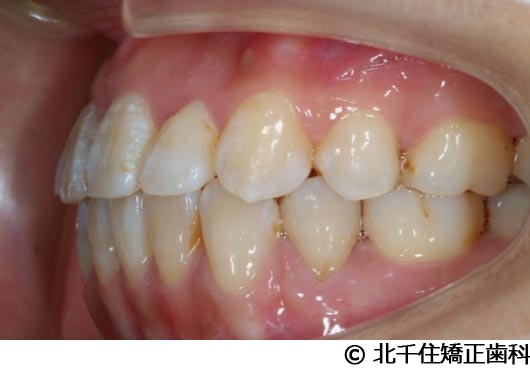

【症例2】上顎前突症

- 治療前

- 治療中

- 治療後

- 治療名

- 上顎前突症

- 費用

- 1,399,000円(税込)

- 期間

- 3年6ヵ月

- 治療回数

- 42回

- 通院頻度

- 1ヵ月ごと

- 年齢・性別

- 19歳10ヵ月・男性(初診時)

治療内容

-

患者様の症状

主訴:出っ歯、口元の突出、横顔をきれいにしたい

治療方法

骨格性の上顎前突、上下顎第一小臼歯4本及び上顎第二大臼歯を抜歯して矯正用アンカースクリューを併用してワイヤー矯正治療(セラミックブラケット)。

治療結果

骨格性上顎前突に対し、抜歯および矯正用アンカースクリューを併用した矯正治療により歯列および咬合関係の調整を行った症例である。治療後は保定装置を使用し、歯列および咬合の安定維持を目的として定期的な経過観察を行っている。

※治療結果は個人差があります。

治療を行う上での注意点(リスク・副作用)

歯磨き不良に伴うカリエスや歯周病、顎関節症、歯根吸収など。